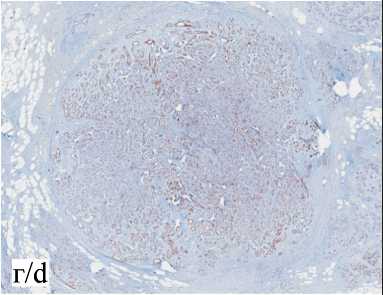

ми 3×0,9×1,5 см. Микроскопическое описание: фрагменты молочной железы с наличием множественных дольково-протоковых структур, часть из которых с пролиферацией люминальных и миоэпителиальных клеток. Отмечается фокус хорошо отграниченного от окружающих тканей новообразования, состоящего из плотно расположенных клеток, с округлыми и овальными гиперхромными ядрами и скудной цитоплазмой, окруженными гиперпластическими миоэпителиальными клетками, формирующими тубулярные структуры. Митотическая активность достоверно не определяется . Края резекции без опухолевого роста. Заключение: морфологическая картина соответствует аденомиоэпителиоме правой молочной железы; простая протоковая гиперплазия (UDH) эпителия протоков правой молочной железы (рис. 8).

Результаты ИГХ-исследования: на периферии железистых структур, а также в окружающей клеточной строме отмечается выраженная ядер-ная экспрессия p63 (polyclonalCell Marque) (рис. 9а) и цитоплазматическая экспрессия Calponin-1(clone EP798Y Cell Marque) (рис. 9б), что демонстрирует наличие миоэпителиальных клеток. В железистых структурах отмечается выраженная диффузная

Рис. 8. Микрофото. Доброкачественная аденомиоэпителиома молочной железы, ×20. Примечание: рисунок выполнен авторами Fig. 8. Microphoto. Benign adenomyoepithelioma of the breast , ×20. Note: created by the authors

Рис. 9. Микрофото. Иммуногистохимическое исследование доброкачественной аденомиоэпителиомы с использованием моноклональных антител Estrogen Receptor, Progesteron Receptor, p63, Calponin-1, CK7, ×20.

Примечание: рисунок выполнен авторами Fig. 9. Microphoto. Immunohistochemical examination of benign adenomyoepithe-lioma using monoclonal antibodies Estrogen Receptor, Progesteron Receptor, p63, Calponin-1, CK7, ×20. Note: created by the authors